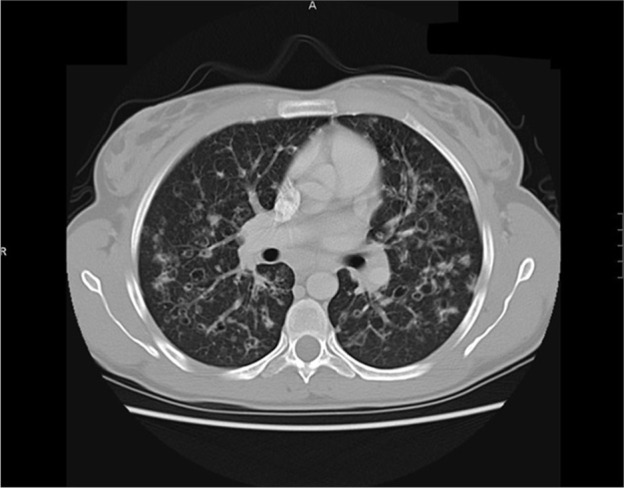

肺朗格汉斯细胞组织细胞增多症(PLCH)是一种罕见的弥漫性肺实质疾病,占所有间质性肺疾病的3%。PLCH既可作为多系统朗格汉斯细胞组织细胞增多症(LCH)的一部分发生,也可作为孤立的肺部疾病发生。在大约50-70%的LCH病例中观察到孤立的肺部受累,发病年龄在20 - 40岁之间无性别差异。吸烟是唯一确定的环境风险因素。PLCH的特点是朗格汉斯细胞浸润,通常以细支气管为中心分布。肺部病变可能发生在慢性全身性疾病之后,也可能是疾病的最初征兆。本研究的目的是(1)报告5例罕见的成人PLCH病例;(2)探讨PLCH与间质性肺纤维化的关系;(3)对PLCH的流行病学、病理生理学、诊断、治疗和预后进行简明的综述,以提高肺科医生和内科医生对PLCH的认识。

Pulmonary Langerhans cell histiocytosis (PLCH) is a rare diffuse parenchymal lung disease representing 3% of all interstitial lung diseases. PLCH occurs either as part of multi-system Langerhans cell histiocytosis (LCH) or an isolated disease of the lung. Isolated involvement of lungs is observed in approximately 50-70% of LCH cases and the age of onset peaks between 20 and 40 years without gender difference. Cigarette smoking is the only identified environmental risk factor. PLCH is characterized by Langerhans cell infiltrates that in general are in a bronchiolocentric distribution. Pulmonary lesions can occur after chronic systemic disease or are an initial sign of disease. The aims of this study are to (1) report five rare cases of PLCH in adults; (2) discuss the relationship of PLCH with interstitial lung fibrosis; (3) provide a concise review of PLCH epidemiology, pathophysiology, diagnosis, treatment, and prognosis to improve the knowledge of PLCH by pneumologists and internal medicine physicians.